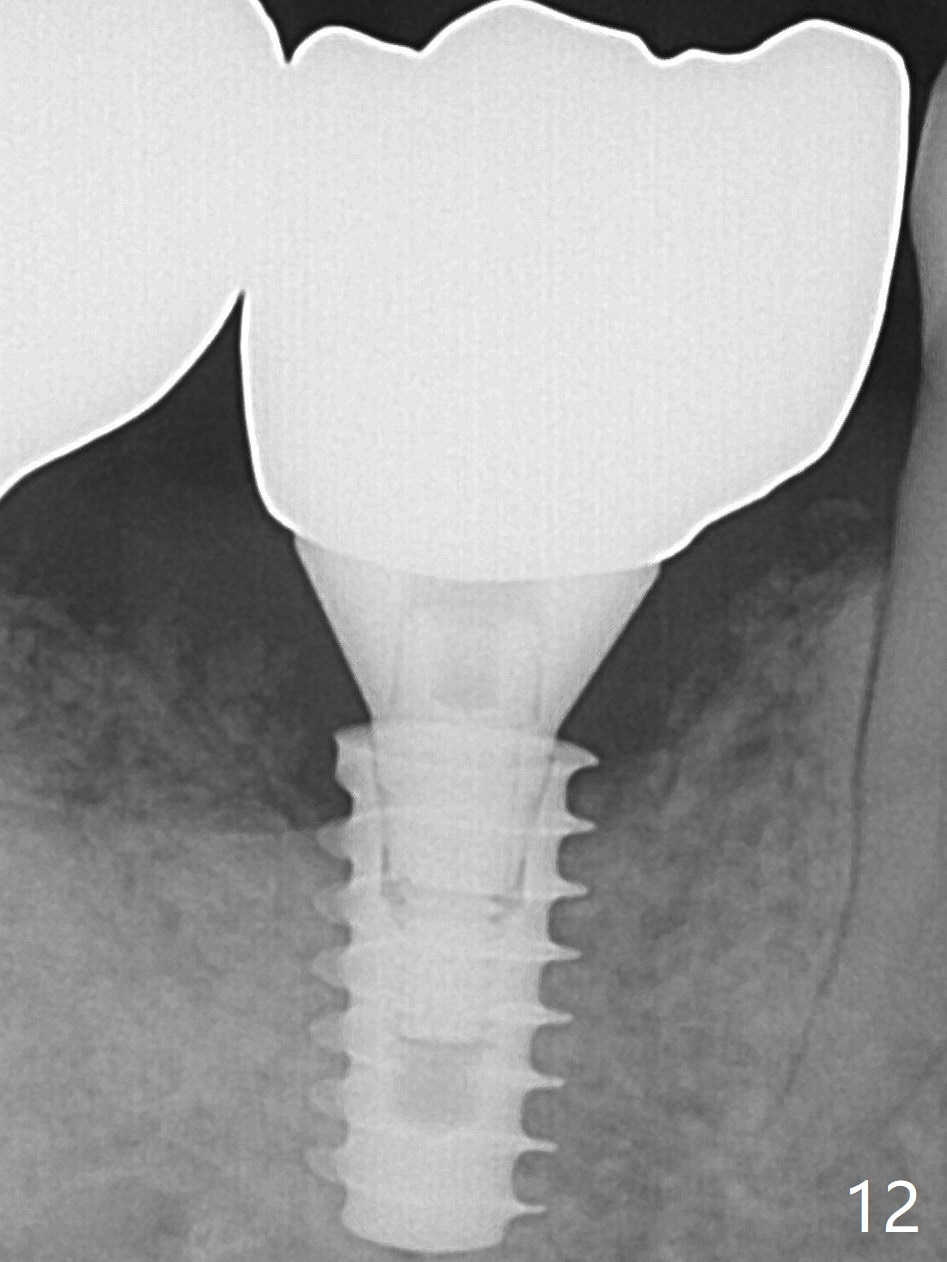

A 5x9 mm implant is placed with packing abundant allograft (.5-1.5 mm) and Osteogen; it appears that 3 to 4 threads (fins) of the implant are engaged to the native bone for primary stability (>40 Ncm).  Later more bone graft is placed distally (Fig.5 arrow).  Abutment: 6.5x5.5(4) mm. The patient in fact masticates on the right side postop.  By the time he returns for provisional revision 1 months 10 days postop, he has mild pain.  There is food entrapment.  The provisional and the abutment are slightly loose, whereas the implant is stable with healing socket.  A healing abutment (6x4 mm) is placed.  The implant appears unstable nearly 5.5 months postop.  The gap between the bone and implant seems to be large (Fig.9).  The implant should have been larger and longer for fast healing.  A healing screw is used instead.  The site heals 10 months postop with an increase in bone density around the implant (Fig.10).  In fact the abutment screw becomes loose 2 months post cementation (1 year postop); it appears that crown/implant ratio is unfavorable (Fig.12).  The implant is slightly placed distally (cantilever).  The tooth #18 is missing (unilateral mastication).